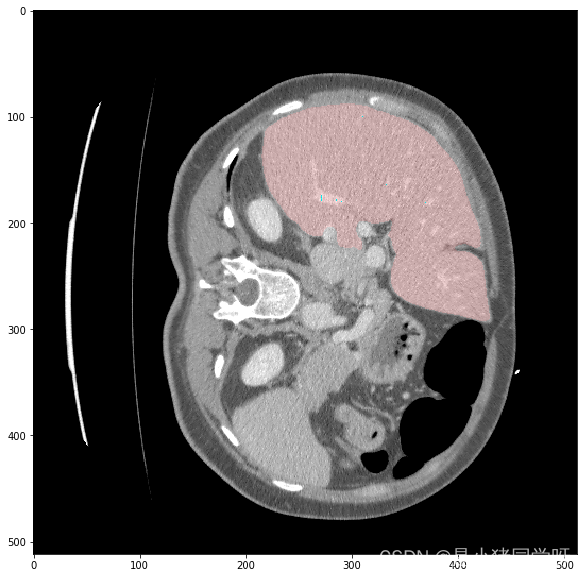

经过测试,肝脏和肝脏肿瘤分割系统的各项功能都能够正常工作,满足用户需求。在白盒测试方面,覆盖了网络结构、特征提取、特征映射、损失函数等方面,没有发现明显的问题。在黑盒测试方面,采用了等价类划分、边界值分析、因果图和错误推测等方法,测试结果表明系统的各项指标均符合要求,没有发现明显的问题。

本次测试结果表明,肝脏和肝脏肿瘤分割系统的各项功能都能够正常工作,满足用户需求。在白盒测试和黑盒测试方面,测试覆盖了网络结构、特征提取、特征映射、损失函数、上传CT影像、查看分割结果、后处理、性能评估、恢复测试、安全测试、强度测试和性能测试等方面,测试结果表明系统的各项指标均符合要求,没有发现明显的问题。